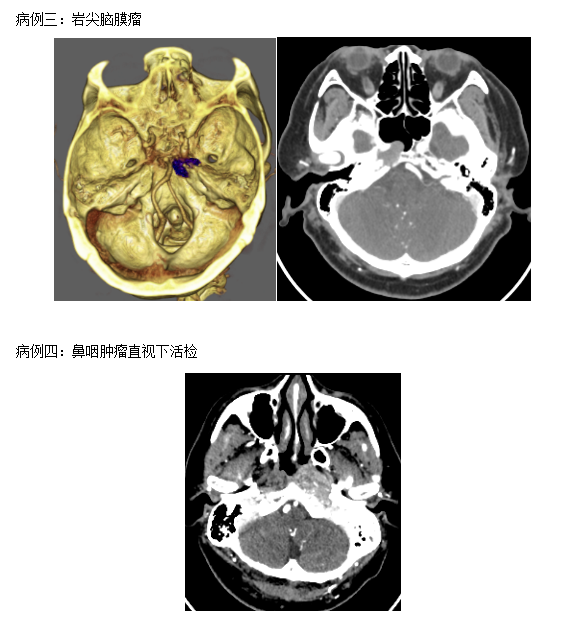

经鼻内镜手术原为耳鼻喉科用来治疗鼻腔副鼻窦疾病的常用手段。现在被神经外科医师所用,取代传统的显微神经外科手术。使用神经内镜通过鼻腔,打开蝶窦,筛窦、进一步磨除斜坡骨质等结构,可以对鼻腔、副鼻窦、前颅窝底、鞍区、斜坡、枕骨大孔区肿瘤进行手术治疗。相比显微神经外科手术,具有对病灶抵近观察,照明好,显露充分,死角少,肿瘤切除率高,对正常结构破坏小,术后恢复快等优点。

颅底肿瘤位置深在,手术显露极为困难。对于颅底脑膜瘤、脊索瘤等开路手术需要磨除颅底骨质,牵拉脑组织等增加显露。近年由于神经内镜器械的进步、解剖认识的更新此区域的肿瘤可以经鼻内镜进行手术,取得了良好的效果。与传统的显微神经外科手舒相比,不用切皮,不用磨除骨质、不用牵拉脑组织就可以切除肿瘤,可以更好的保护好神经、血管等重要结构,利用脂肪、阔筋膜、带蒂鼻中隔粘膜瓣修补,可以预防脑脊液漏。